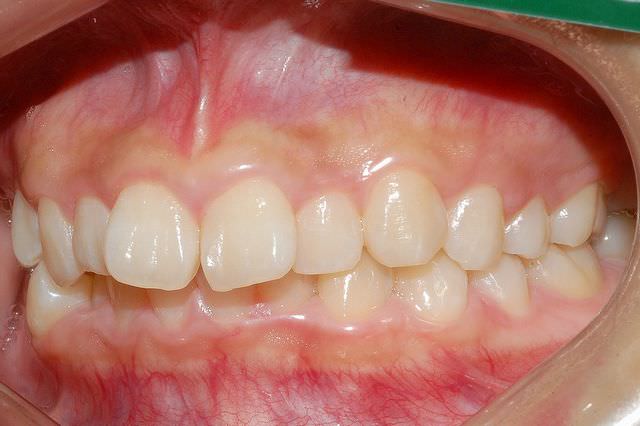

上顎前突 治療前

主訴 前歯が出ているのが気になる口が閉じにくい

診断名あるいは主な症状 上顎前突

年齢 11歳4ヶ月

治療に用いた主な装置 ブラケット装置 スタンダードエッジワイズ法

抜歯部位 上下両側第一小臼歯

治療期間 2年11ヶ月

治療費概算 70万+月々の調整料

リスク副作用 歯の根が吸収して短くなる場合があります。

歯茎が痩せて下がる場合があります。

舌で歯を押す唇を噛む等の癖が改善されない場合は、治療期間が長引く場合があります。

定期的に通院できない、キャンセルが多い場合は治療期間が長引きます。